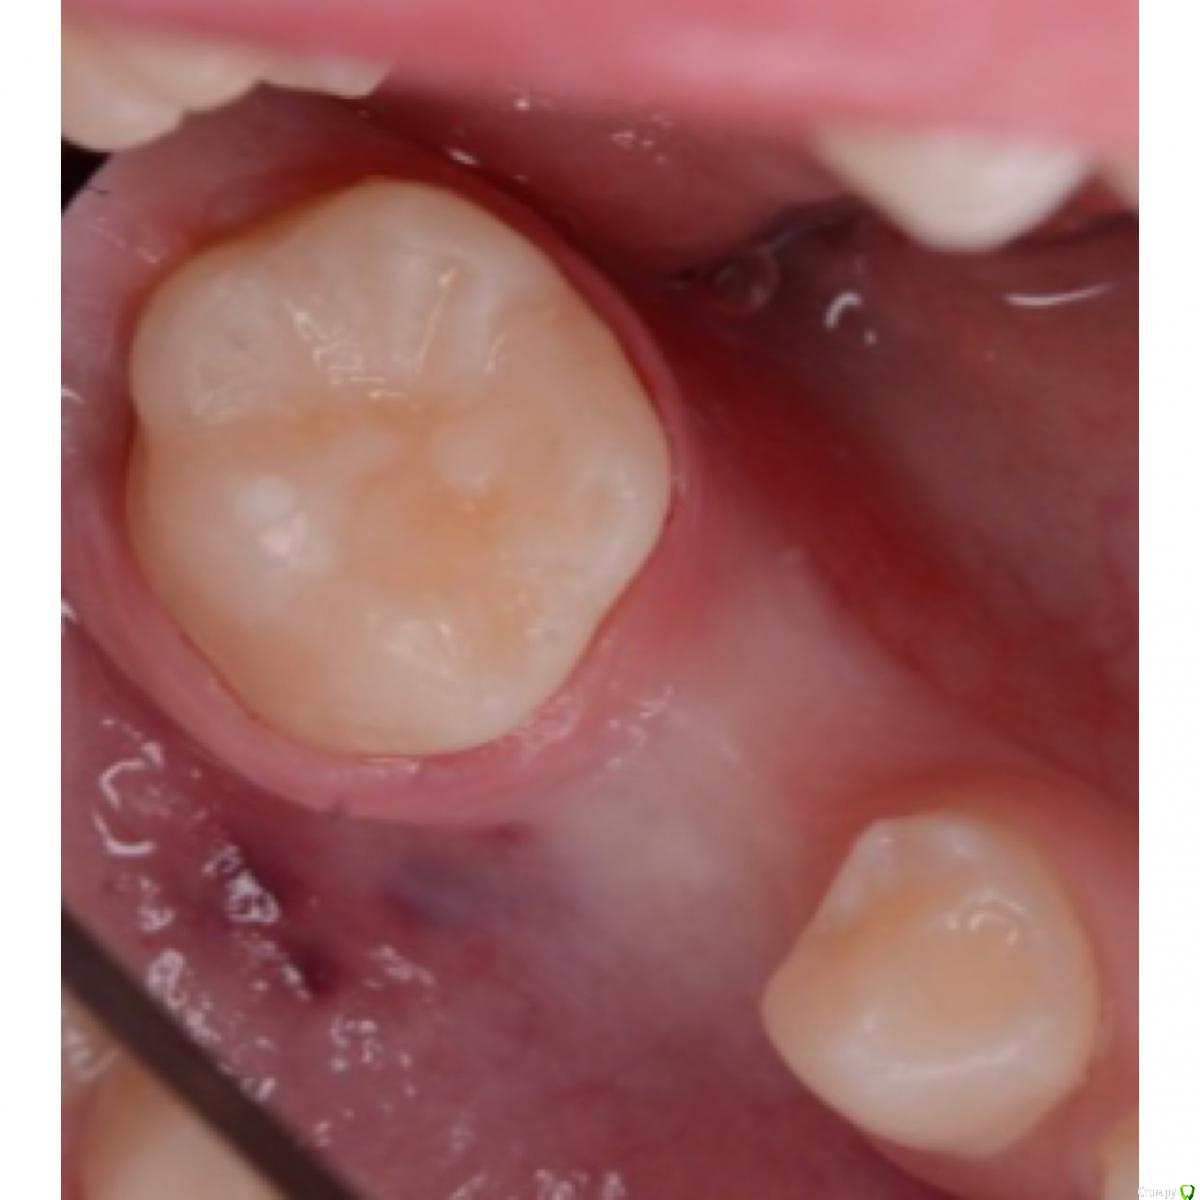

CRAZYDUCK Опубликовано 12 мая, 2018 Автор Поделиться Опубликовано 12 мая, 2018 Вероничке 4,5 годика . Очень веселая и контактная девчушка ( такой пирожочек сладенький , булочка 5 Ссылка на комментарий

CRAZYDUCK Опубликовано 12 мая, 2018 Автор Поделиться Опубликовано 12 мая, 2018 К предыдущему посту Но предстоящее лечение 8.5 все же сложное и это первый опыт . Как он пройдёт ? Не испугается ли онемения ? «Высидит» ли за один раз все ? Старшая сестричка Вероники очень боится лечить зубы ( с третьего визита позволила только почистить зубы ) . Был Негативный опыт , может повезёт и покажу и сестричку .Вероника молодцом ! Только устала , но выбор подарка после лечения ее взбодрил .Теперь по делу - экстирпация во временных зубах - это глубокая или очень глубокая ампутация. Наша задача удалить нерв , не выходя за апекс временного ( примерно на 2/3 длины канала ), моем гипохлоритом (!!!!) , сушим пылесосом ( можно одеть канюлю от метапекса - метапасты на насадку пылесоса и просушить в канале ( я ещё досушиваю бумажными пинами).Апекслокатор - не нужен ! Главное , чтобы из канала не кровило и было сухо . Инструментальная обработка Sx ( устьевик), потом ручными ( я чаще до 25.02 максимум прохожу ),пломбирую пастой Йодотин ( аналог метапекса), проверяем вне полости рта - идёт ли паста из канюли - вводим в устье , аккуратно выдавливаем - появилась паста в устье - начинаем вытягивать канюлю из канала ( одновременно выдавливая пасту ). Делаем то же самое с другими каналами и убираем излишки . Я перекрываю кальцимолом устья , под коронку восстанавливаю IRM. Фиксация Коронки без коффердама . Излишки цемента из межзубных промежутков убираю флоссом, посередине нитки делаем узелок , чтобы он помог вывести излишки . Фиксирую на айрекс цем .( с дёсны излишки цемента не убрала - устала Вероничка). Ссылка на комментарий

crown Опубликовано 14 мая, 2018 Поделиться Опубликовано 14 мая, 2018 А что пломбу не поставили? Ссылка на комментарий

CRAZYDUCK Опубликовано 14 мая, 2018 Автор Поделиться Опубликовано 14 мая, 2018 А что пломбу не поставили?Стенки тонкие , не простоит реставрация долго . Лучше лечить один раз временный зуб . Ссылка на комментарий